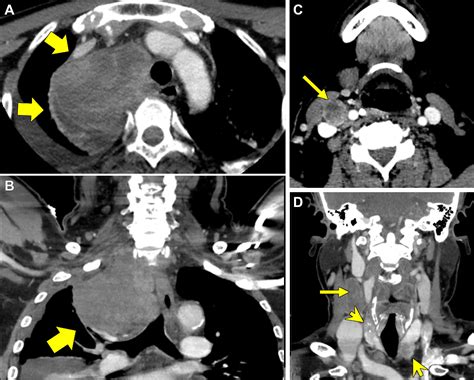

Diagnostic Approaches and Staging

Accurate diagnosis is the cornerstone of effective management. Physicians utilize a combination of imaging and molecular testing to map the extent of the disease. Because thyroid cancer can be slow-growing, imaging plays a vital role in monitoring how the cancer behaves over time.

PET/CT Scan Helps locate metabolic activity in areas where the cancer may have spread.

Surgery and External Beam Radiation

Surgery may still be utilized to remove large metastatic deposits, especially if they are causing structural damage or compression in the neck or bone. External beam radiation is frequently used to manage localized pain caused by bone metastases or to prevent neurological complications by shrinking tumors near the spinal cord.